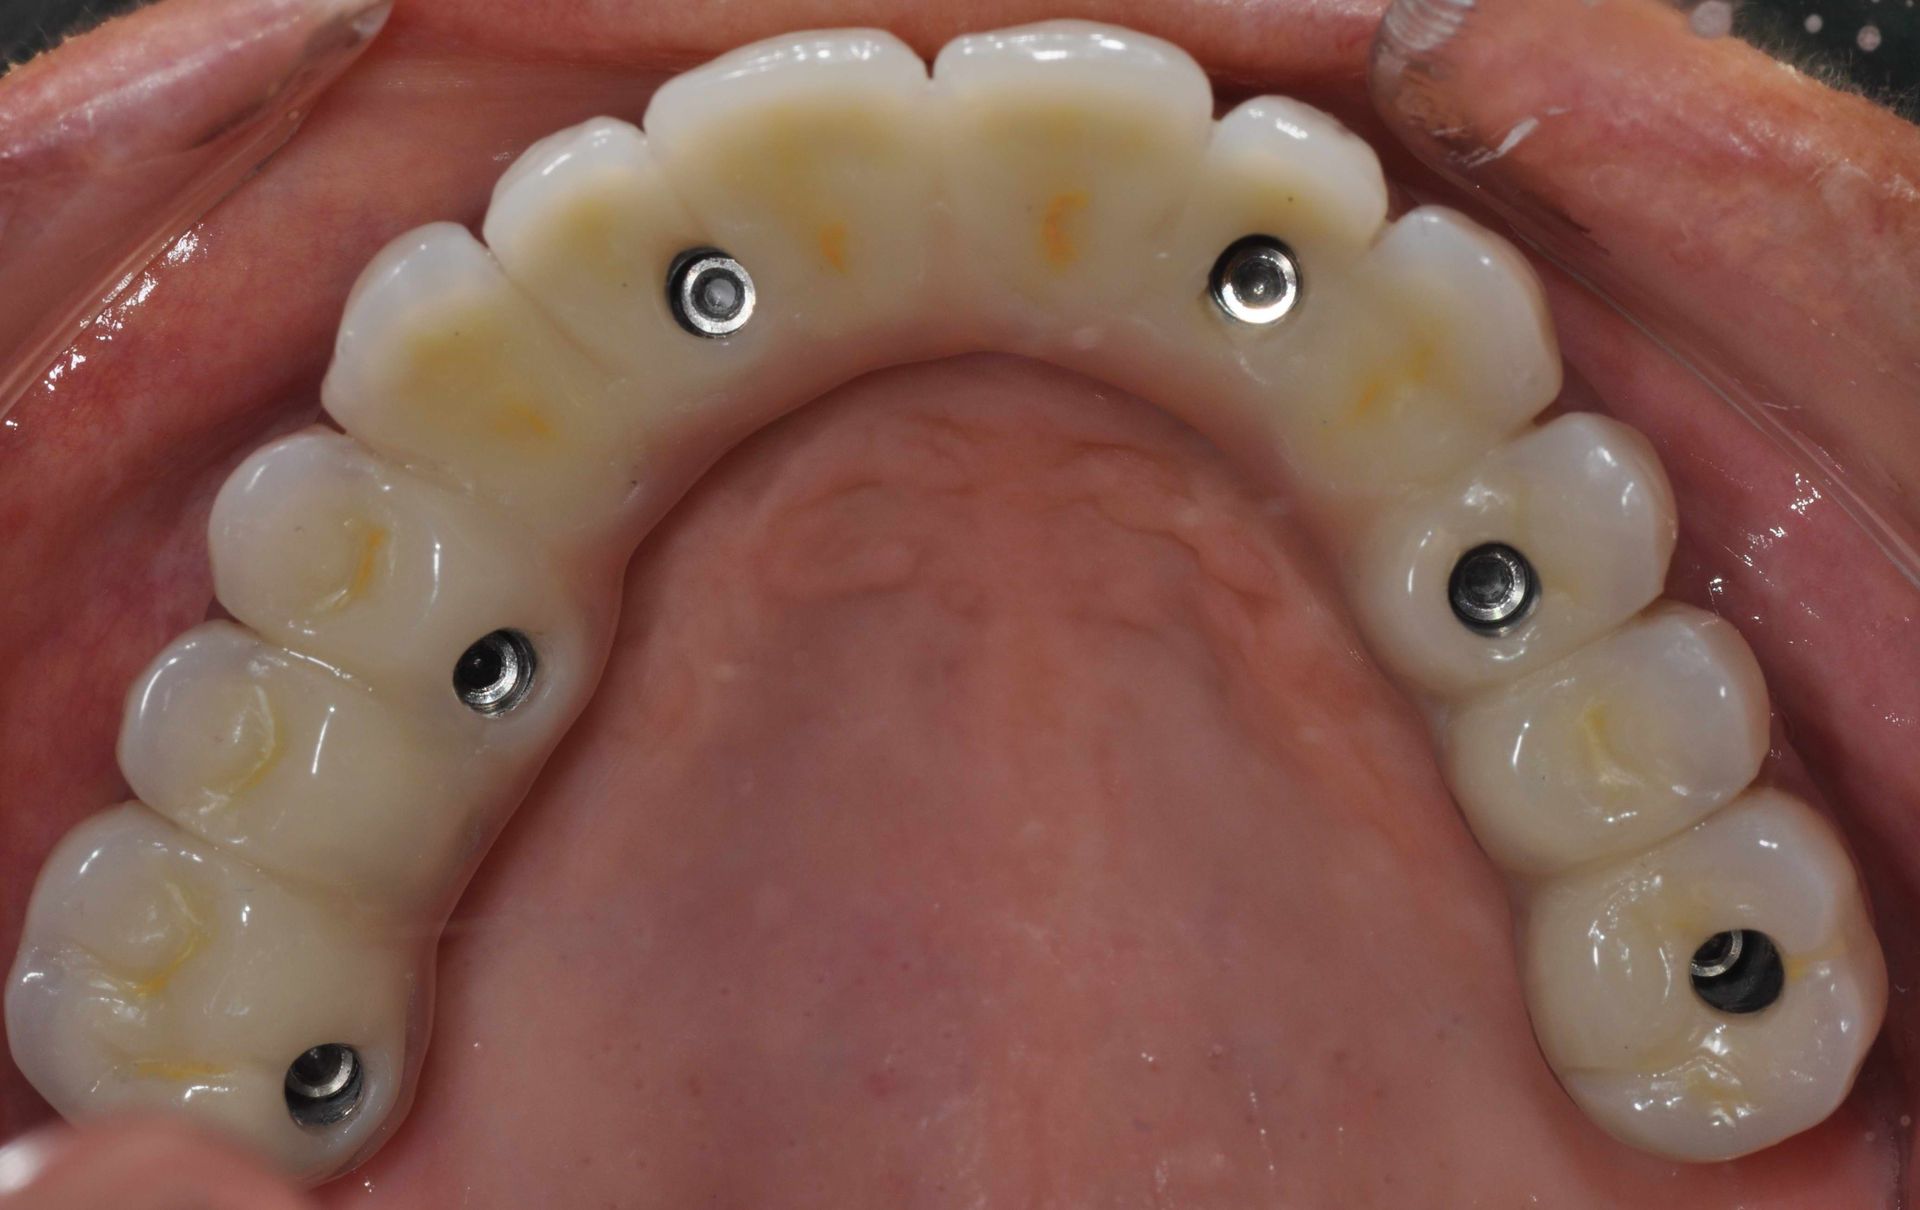

Implantologia

L'implantologia è una branca dell'odontoiatria che si occupa della sostituzione dei denti mancanti attraverso l'inserimento di impianti dentali. Questi impianti, realizzati in titanio biocompatibile, fungono da radici artificiali su cui vengono fissate protesi dentarie come corone, ponti o dentiere. L'implantologia offre una soluzione stabile e duratura per ripristinare la funzionalità masticatoria e l'estetica del sorriso, migliorando significativamente la qualità della vita dei pazienti.